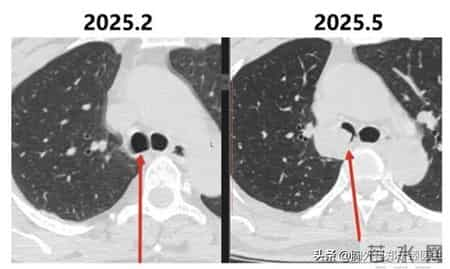

手术是2023年11月做的,2025年的2月复查时还是一切正常,但在2025年5月复查时,就发现右肺的主支气管出现软组织结节,直径22 mm,符合复发表现。

这个病例当时给我留下了非常强烈的印象。

它告诉我们,囊腔型肺癌是有风险的。而且这样的风险往往是我们无法计算的,就算能计算出来,它也是不准确的。